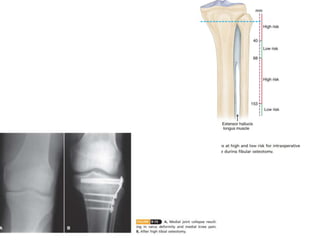

Normally, there is valgus alignment of 5 to 8 degrees in

the tibiofemoral angle as measured on radiographs taken in

the weight-bearing position. The amount of correction of the

arthritic knee needed to achieve a normal angle is calculated,

and an additional 3 to 5 degrees of overcorrection is added

to achieve approximately 10 degrees of valgus. With a varus

deformity, the only limitation in the amount of correction

from a valgus osteotomy is the size of the bone wedge that

can be taken proximal to the patellar tendon.

 roughly 1 degree of correction for each 1 mm of length at

the base of the wedge (e.g., 20 degrees of correction =a

20-mm base of the wedge). This is true only if the tibia is

57 mm wide, however, and we prefer using exact

measurements for the width of the base of the osteotomy,

with a right triangle con-structed from a preoperative

drawing or the

 formula W =diameter ×0.02 ×angle or tangent tables.

 Alternately, full-length, near actual size, standing

anteroposterior radiographs can be used to determine the

size of the wedge needed. The desired alignment, based on

the mechanical axis from the center of the femoral head

through the knee to the center of the ankle, can be

achieved by cutting the appropriate-sized wedge from the

proximal tibia.